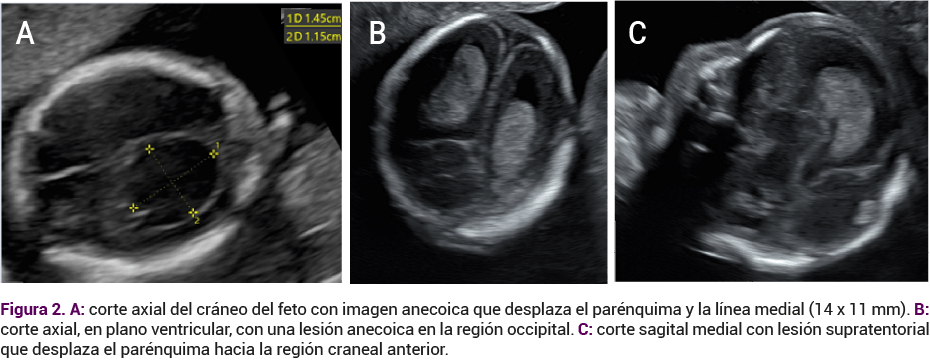

A su ingreso a la clínica se le practicó un ultrasonido obstétrico institucional por parte de un especialista en medicina materno fetal. Inicialmente se documentó la existencia de un feto con actividad cardiaca adecuada, peso estimado de 212 gramos, crecimiento adecuado, con situs solitus corte de cuatro cámaras normales, simétricas, campos pulmonares de ecogenicidad normal (Figura 1). En la región occipital derecha de la cabeza del feto se observó una imagen quística anecoica supratentorial, localizada en el espacio subaracnoideo que desplazaba al parénquima hacia la región anterior y a la línea media hacia el lado contralateral, sin evidencia de flujo al Doppler color, que midió 16 x 11 mm (Figura 2). En ese momento la imagen era sugerente de un hematoma subaracnoideo occipital derecho. Los tálamos, pedúnculos cerebrales, tabique doble, vertical y triangular se localizaron en la línea media. La fosa posterior era de aspecto normal. El sistema ventricular no estaba dilatado. La calota fetal se observó íntegra. El resto del estudio morfológico fetal se advirtió en parámetros de normalidad.

<strong>Figura 2</strong>

Figura 2.